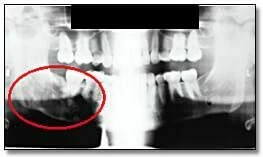

Hình ảnh thể hiện mức độ tiếp xúc quá mức có thể dẫn đến việc không phát hiện được các đặc điểm bệnh lý. Hình 34a là phiên bản nâng cao kỹ thuật số của bức ảnh 34b. Có thể thấy Hình 34b bị phơi sáng quá mức khi chụp, thể hiện rõ ràng sự xuất hiện của một vùng bức xạ gây ra sự mở rộng và mỏng đi của phần xương bên dưới của hàm phải – những đặc điểm không thể hiện rõ trên bản gốc.

Ví dụ về hình ảnh toàn cảnh thiếu sáng

Hình ảnh với liều tia không đủ có thể dẫn đến không phát hiện được các đặc điểm bệnh lý. Hình 35a là một phiên bản nâng cao kỹ thuật số. Chúng ta có thể dễ dàng thấy chiếc răng hàm thứ ba bên phải bị tác động mà bị mờ đi trên bản gốc. Sự tăng cường này cũng chứng tỏ rõ ràng bệnh nhân có một bệnh lý liên quan đến răng hàm dưới thứ hai bên phải.